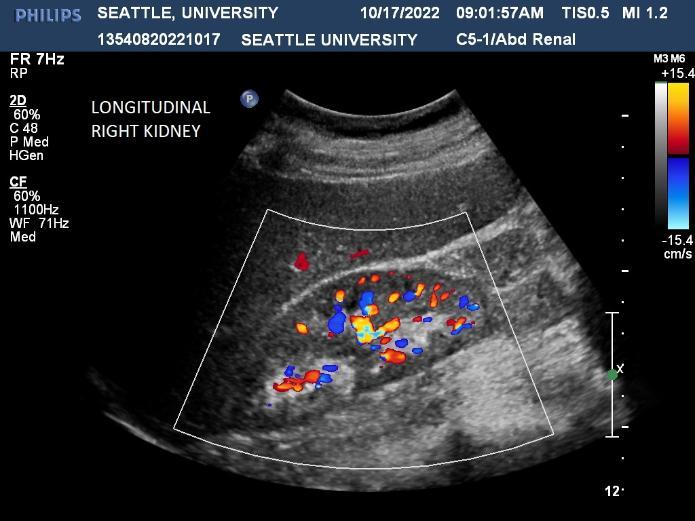

Ultrasound is a non-invasive diagnostic tool that uses high-frequency sound waves to propagate images of organs and tissues within the body. The Diagnostic Ultrasound program at Seattle University offers three distinctive track specializations in General (abdomen extended, OB/GYN) Vascular and Cardiac sonography.